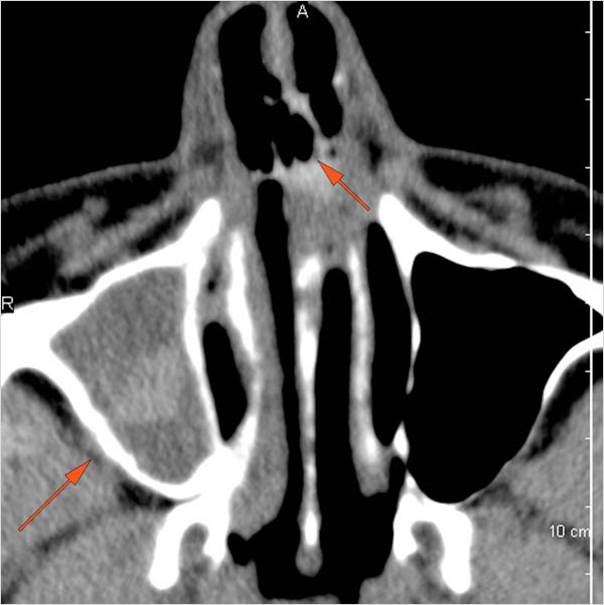

Nasal Cavity and Nasolacrimal Drainage System

There is mucoperiosteal thickening in the nasal cavity. [Yes/No]

There is ulceration or erosion of the nasal septum or turbinates. [Yes/No]

There is mucosal thickening of the posterior lateral walls of the nasal cavity, cribriform plate or the face of the sphenoid bone. [Yes/No]

There is infiltration of the fat surrounding the nasolacrimal sac. [Yes/No]

There is infiltration of soft tissues or bone erosion along the nasolacrimal fossa or canal. [Yes/No]

Sinuses

There is soft tissue swelling anterior to the frontal sinus or in the soft tissues surrounding the maxillary sinuses. [Yes/No]

There is mucoperiosteal thickening in the sinuses. [Yes/No]

There is mucosal enhancement in the sinuses. [Yes/No]

There is an air fluid level in the frontal sinus. [Yes/No]

There is bone erosion along the walls of any affected sinuses. [Yes/No]

There is an appearance of bone expansion, due to regressive remodeling and suggestive of pre-existing mucocele, along the walls of any affected sinuses. [Yes/No]